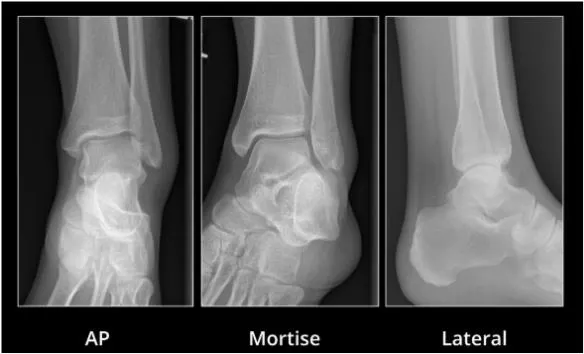

AP

Identifies fractures of malleoli, distal tibia/fibula, plafond, talar dome, body and lateral process of talus, calcaneous

Mortise

Ankle 15-25 degrees internal rotation

Evaluate articular surface between talar dome and mortise

Lateral

Identifies fractures of anterior/posterior tibial margins, talar neck, displacement of talus